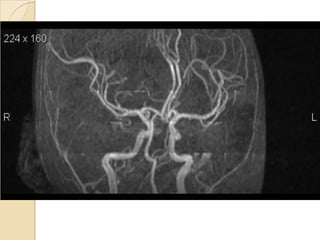

Arteries of the brain (cranial view) - MRA

1. Anterior cerebral artery

2. Anterior communicating artery

3. Basilar artery

4. branches (in insula) of middle

cerebral artery

5. Cavernous portion of internal

carotid artery

6. Cervical portion of internal carotid

artery

7. Genu of middle cerebral artery

8. Intracranial (supraclinoid) internal

9. Middle cerebral artery

10. Ophthalmic artery

11. Petrous portion of internal carotid

12. Posterior cerebral artery

13. Posterior cerebral artery in ambient

cistern

14. posterior cerebral artery in

interpeduncular cistern

15. Posterior communicating artery

16. Posterior inf cerebellar artery.

17. Quadrigeminal portion of posterior

18. Superior cerebellar artery

19. Vertebral artery